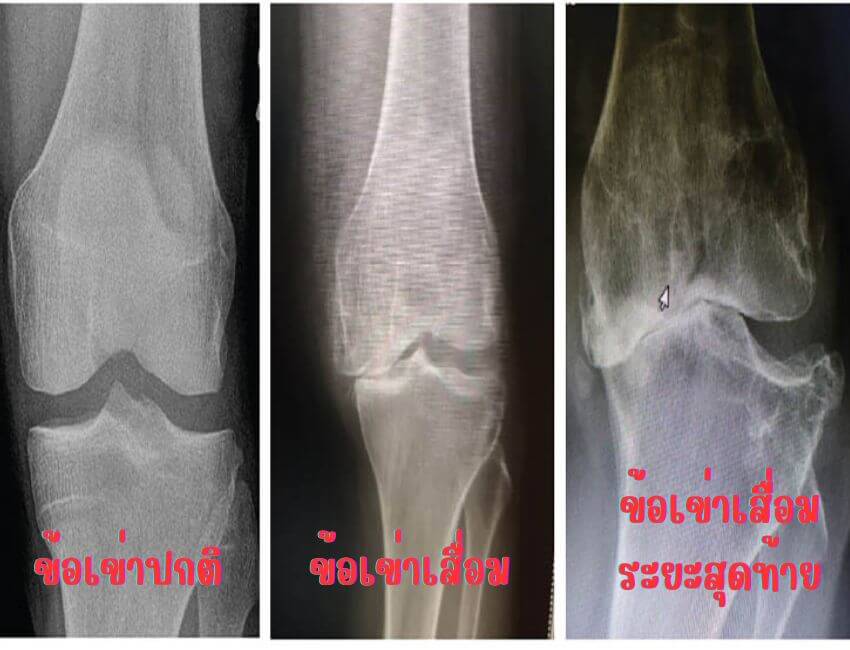

โรคข้อเข่าเสื่อม คือ โรคที่เกิดจากความเสื่อมและสึกหรอของกระดูกอ่อนผิวข้อ ( articular cartilage) โดยมีการเสื่อมสึกหรออย่างช้าๆต่อเนื่องตามกาลเวลาที่ผ่านไป ทั้งทางด้านรูปร่าง และโครงสร้าง รวมถึง กระดูกบริเวณใกล้เคียง เช่น ขอบกระดูกมีการหนาตัวขึ้น และอาจมีกระดูกงอก มีการเปลี่ยนแปลงของน้ำไขข้อ ทำให้คุณสมบัติการหล่อลื่นลดลง ผู้ป่วยจะมีอาการปวดข้อเข่า ข้อเข่าฝืด เคลื่อนไหวข้อได้ลดลง และเมื่อเวลาผ่านไปสักระยะ จนไม่มีผิวกระดูกอ่อน เนื้อกระดูกจะมีการชนกันเวลารับน้ำหนัก จะมีผลทำให้ข้อผิดรูปและพิการในที่สุด

ระยะสุดท้าย ถ้าไม่ได้รับการแก้ไข จะเกิดการสลายของเซลล์ผิวกระดูกอ่อน สูญเสียโปรตีนและของเหลวในข้อเข่า (synovial fluid) ทำให้เกิดการโก่งผิดรูปของข้อเข่า ข้อเข่าจะไม่สามารถเคลื่อนไหว งอเหยียดเข่าได้เหมือนปกติ

จากอาการดังกล่าว เราจะแบ่งอาการโรคข้อเข่าเสื่อมออกเป็น 4 ระยะ

ระยะที่ 4 ผู้ป่วยจะเริ่มเคลื่อนไหวลำบาก เดินไม่ไหว